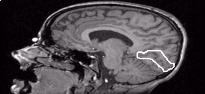

The aim was to model a particular region of cortex, and in particular, the visual cortex. A three dimensional reconstruction of the surface of the visual cortex surrounding the calcarine fissure was created. Twelve sagittal MR slices which contained the calcarine fissure in the right hemisphere of the brain were used. From each of these slices, the calcarine fissure and surrounding grey matter (region inside the white circle as shown in the following image) were extracted using the software Photoshop.

MR Slice Marked with Extracted Region

The stretched appearance of the above image is because the original MR scans were spaced vertically 1.5 mm apart, whereas in the other directions, they were spaced 1.0 mm apart. The image hasn't yet been transformed to adjust for these different spacings.